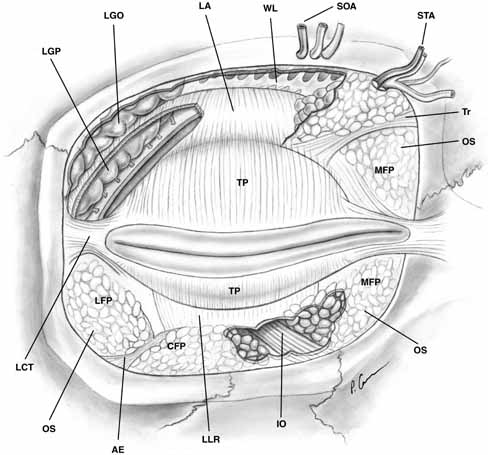

lateral orbital rim11 (see Fig. 7).  Fig. 7 Anterior view of orbital septum and related structures. The medial deep

orbital insertion of the orbicularis muscle carries the orbital septum

behind it. The septal attachments to the levator aponeurosis in the

upper lid and inferior tarsus in the lower lid are also demonstrated, as

well as the anatomic relationships to the structures of the upper lid. (AE, arcuate expansion of the inferior oblique; CFP, central fat-pad; IO, inferior oblique muscle; LA, levator aponeurosis; LCT, lateral canthal tendon; LFP, lateral fat-pad; LGO, lacrimal gland orbital lobe; LGP, lacrimal gland palpebral lobe; LLR, lower lid retractors; MCT, medial canthal tendon; MFP, medial fat-pad; OS, orbital septum; STA, supratrochlear artery, nerve, vein; SOA, supraorbital artery, nerve, vein; TP, tarsal plate; Tr, trochlea; WL, Whitnall's ligament) Fig. 7 Anterior view of orbital septum and related structures. The medial deep

orbital insertion of the orbicularis muscle carries the orbital septum

behind it. The septal attachments to the levator aponeurosis in the

upper lid and inferior tarsus in the lower lid are also demonstrated, as

well as the anatomic relationships to the structures of the upper lid. (AE, arcuate expansion of the inferior oblique; CFP, central fat-pad; IO, inferior oblique muscle; LA, levator aponeurosis; LCT, lateral canthal tendon; LFP, lateral fat-pad; LGO, lacrimal gland orbital lobe; LGP, lacrimal gland palpebral lobe; LLR, lower lid retractors; MCT, medial canthal tendon; MFP, medial fat-pad; OS, orbital septum; STA, supratrochlear artery, nerve, vein; SOA, supraorbital artery, nerve, vein; TP, tarsal plate; Tr, trochlea; WL, Whitnall's ligament)

In the lower eyelid, the septum inserts onto the inferior border of tarsus

after joining with the lower lid retractors 4 to 5 mm below the tarsus. The

superior orbital septum does not insert onto the superior tarsal

plate because of the intervening levator aponeurosis; rather it inserts

on the aponeurosis about 10 mm above the superior eyelid margin, or 2 to 5 mm

above the superior tarsal border in non-Asians11 (see Fig. 8). In Asian lids, the orbital septum fuses to the levator aponeurosis